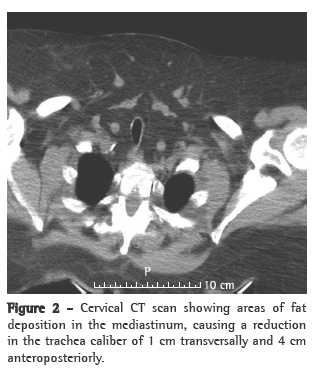

The clinical status of the patient progressively improved, with subsequent reduction in BiPAP pressures and in the use of the ventilator, which was interrupted on post-admission day 6 due to the appearance of facial ulcerations caused by the nasal mask. During the first night without noninvasive ventilation, there were long periods of oxygen desaturation (SpO2 < 88%) and snoring. The patient was then submitted to cervicofacial CT (Figures 1 and 2) and a cardiorespiratory sleep study.

The sleep study lasted approximately 8 h, revealing severe obstructive sleep apnea (apnea-hypopnea index: 37 events/h; obstructive apnea index: 29 events/h; median oxygen saturation during sleep: 88%; oxygen desaturation index: 51%/h; and minimum SpO2: 51%). The CT scan revealed various areas of fat deposition in the mediastinum, causing a reduction in the trachea caliber of 1 cm transversally and 4 cm anteroposteriorly. Continuous positive airway pressure (CPAP) titration was carried out on the second night, and the patient was discharged. At home, the patient remained on BiPAP ventilation (EPAP: 8 cmH2O; IPAP: 16 cmH2O), delivered via nasal pillows (Figure 3).